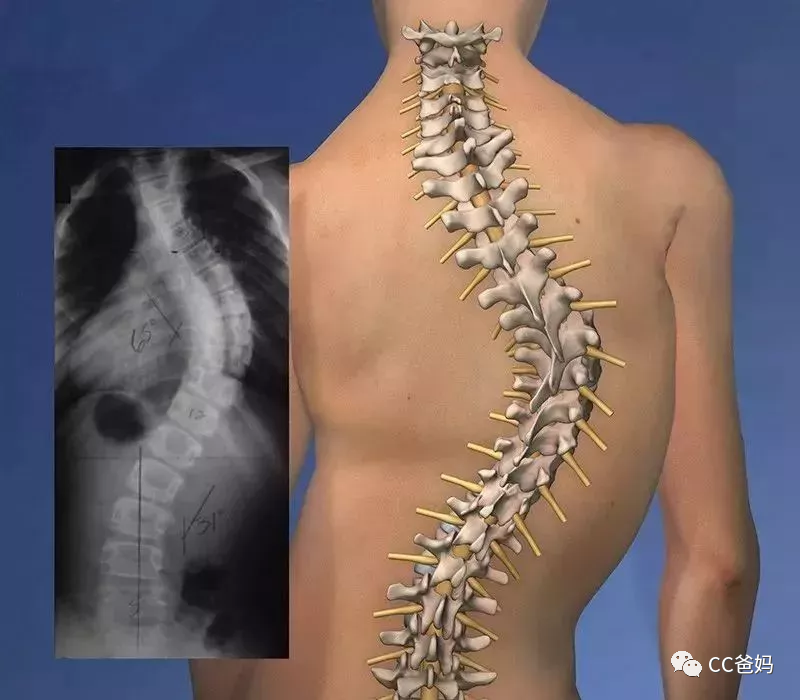

脊柱侧弯儿童

5岁男孩严重脊柱侧弯超100度高难度手术助其矫形

[精] 脊柱弯曲,你叫我如何有个美好的童年!

儿童脊柱侧弯竟和这个姿势有关?家长快来看看

脊柱侧弯,影响儿童健康的大"杀手"75 72《"健 - 抖音

每6个孩子就有1个脊柱侧弯只因10岁前父母忽略了这一点